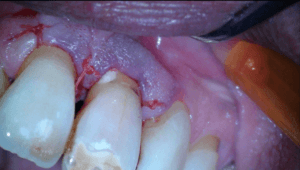

Na anesthesie volgde een flapoperatie om de pocket te openen. Al snel werd een breuk zichtbaar in het element. Maar hoe ver liep de barst door?

Voorzichtig verwijderden we alle granulatieweefsel en spoelden we het schoon. Wat we zagen had ik nog nooit eerder waargenomen. Er zat een min of meer circulaire barst wat eigenlijk een los zittend stukje dentine was.

Na het wegfrezen van het losse stukje vulden we het defect op met composiet. We werken de composiet af met fijne diamantjes en handscalers. Een superscherp geslepen handinstrument kan uitstekend worden gebruikt bij het afwerken van composietvullingen. Wel alleen vlak na het polymeriseren, dan is composiet nog te scalen.

Na polijsten hechtten we de flap en maakten we een afspraak voor een week later.